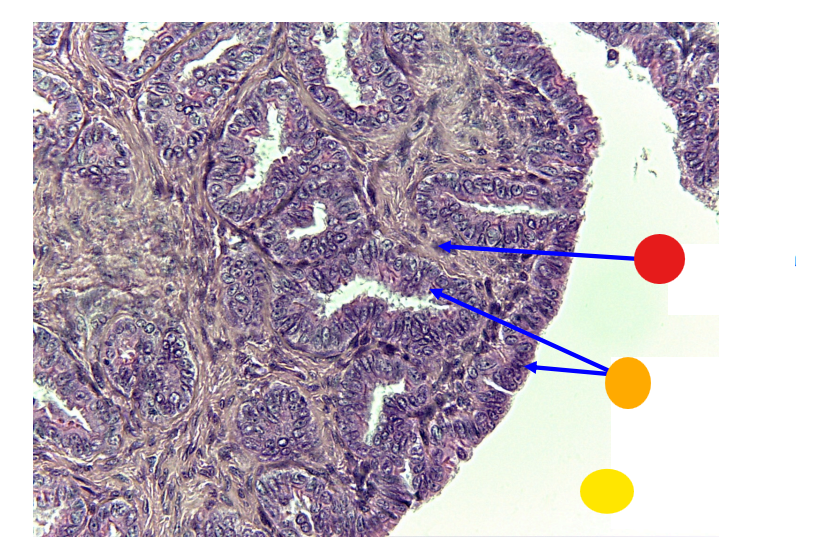

red

granulosa cells

orange

primary oocyte

what is this

primary follicle

red

granulosa cells

orange

thecal cells

yellow

zona pellucida

What is this

secondary follicle